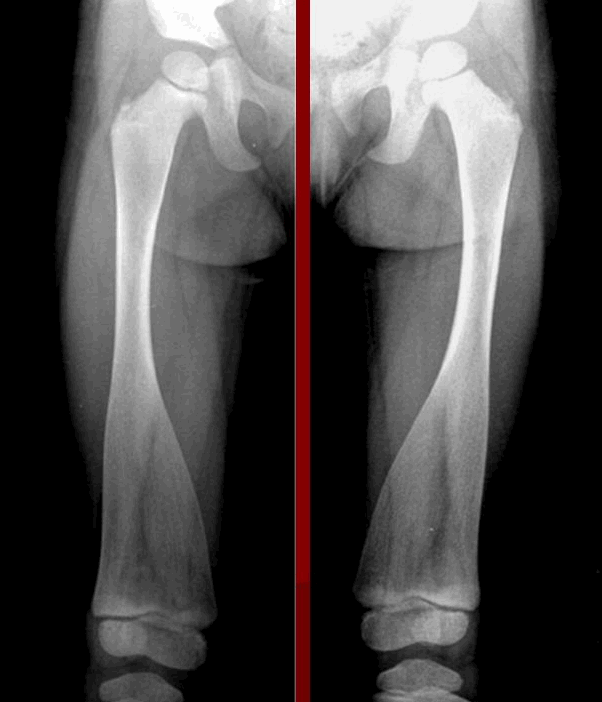

Диагноз метафизарной дисплазии обычно ставят при проведении рентгенографии по несвязанным причинам. Рентгенологические изменения являются патогномоничными. Длинные кости недостаточно деформированы, и наружный слой кости, как правило, тонкий. Трубчатые кости ног имеют грубое расширение книзу, подобно колбе Эрленмейера, особенно в дистальной части бедренной кости. Кости малого таза и грудной клетки расширены. Тем не менее, череп, в основном, не затронут.

При метафизарной дисплазии происходит генетическое нарушение в строении костей скелета. При этом практически не меняется форма черепа, не возникают мутации нижней или верхней челюсти, характерные для краниометафизарной формы.

Заболевание сложно обнаружить без рентгенологического исследования. Среди характерных признаков – конусообразное расширение в трубчатых костях нижних конечностей. Они по форме начинают напоминать стеклянные колбы, используемые в лабораториях.

Симптомы метафизарной дисплазии

Характерным признаком заболевания является сильное смещение трубчатых костей при одновременном и значительном расширении колбы Эрленмейера в ногах. Особенно симптомы выражены при поражении бедренной части. При метафизарной дисплазии негативные изменения в строении черепа минимальны. В редких случаях сильно выступают лобные доли над глазницами, создавая асимметричное строение лица.

Болезнь Пайла

В отличие от других форм метафизарной дисплазии при болезни Пайла наблюдается аномальный рост трубчатых костей. У пациента появляется выраженная деформация коленных суставов, сколиоз 1-2-й степени. Уже в 8−9 лет у детей развиваются дисплазия тазобедренных суставов, поражение метафизов большеберцовых костей. Среди характерных симптомов: